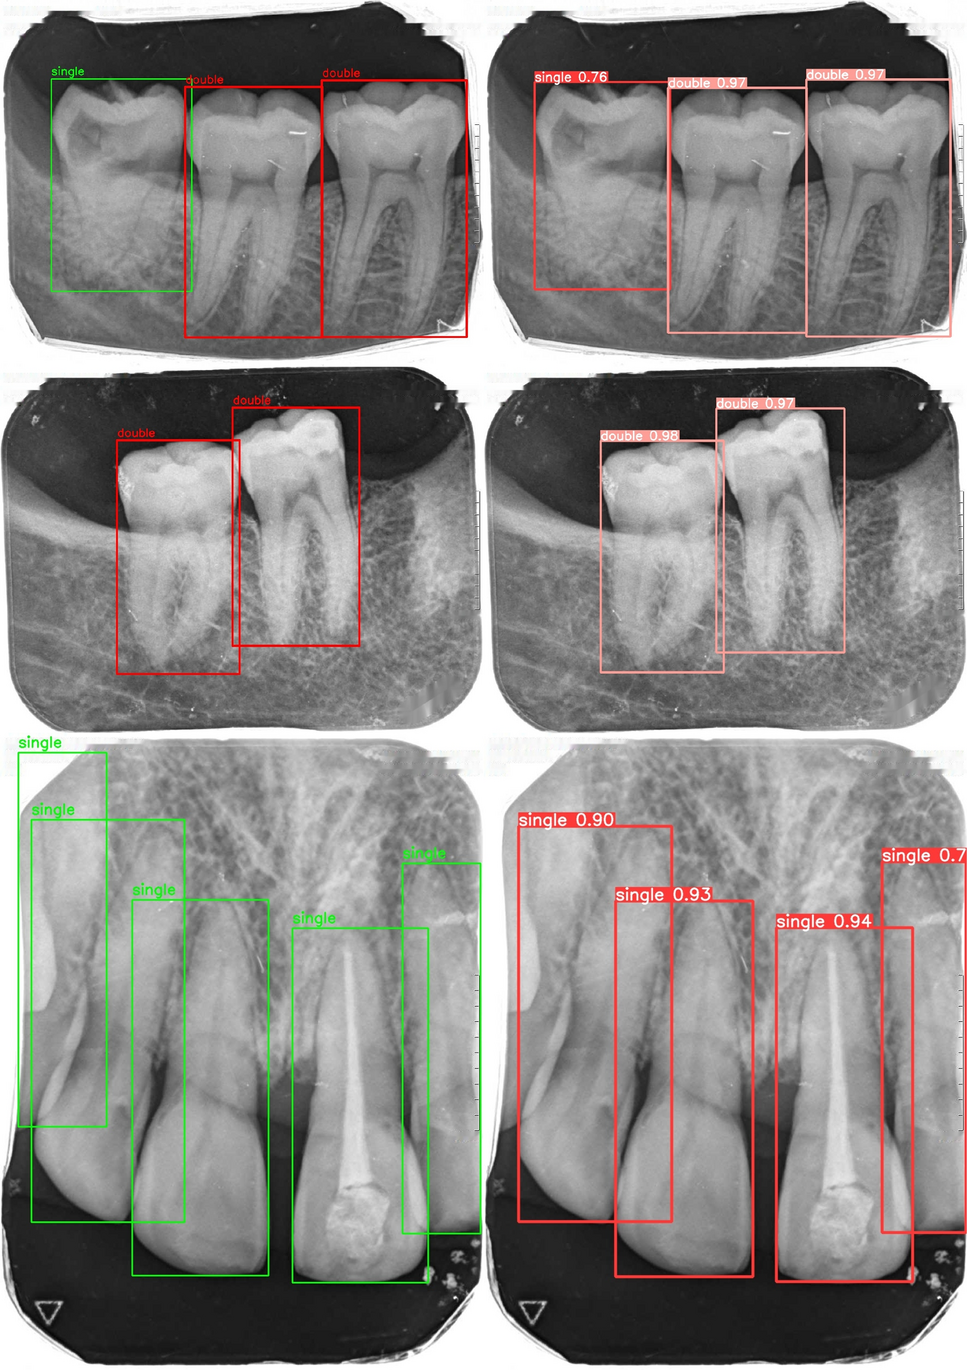

Fig. 7

Comparison of ground truth (left) and predicted (right) tooth detection.